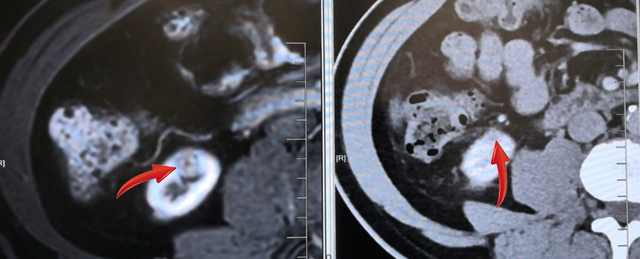

无独有偶,62岁的金先生,在放射科诊查泌尿系平扫+增强CT+CTU中:患者右肾上极肿块,囊实性,包膜完整,直径约1.5cm肿瘤,与周围少粘连;入院后完善术前检查,排除手术禁忌证后在全麻下行“腹腔镜下肾部分切除术”,手术顺利,术后恢复良好。病理显示:透明细胞性肾细胞癌。

由于显影、诊断能力等各项不确定因素的存在,通常肿瘤在3cm以下很容易被漏诊,这次9.5mm肿瘤被探查出,放射科医生火眼金睛的背后是专业、细心和责任!